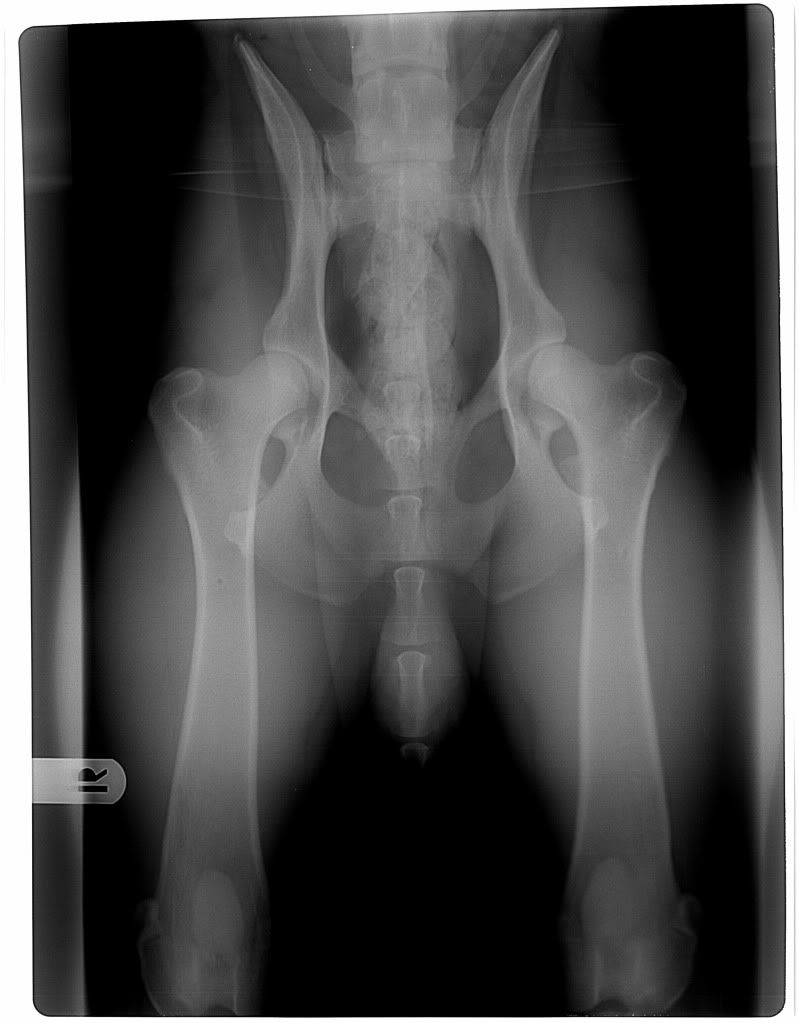

@Gaby. Je ziet dat niet zozeer aan de ruggegraat danwel aan de uitstekende puntjes van het bekken die aan twee kanten even ver achter het bovenbeen moeten liggen en aan de twee openingen van het bekken die exact gelijk moeten zijn. Daarbij moet de knieschijf zichtbaar zijn en midden boven de knie liggen.

Dit zijn die van Tapas trouwens (HD-A, NBW 40):

ondanks het feit dat het slechte foto's zijn ( schandalig slecht zelfs) zie je wel dat de heupen niet helemaal goed zijn. Je ziet puntjes aan de bolletjes en afvlakkingen op de bollen en ze passen niet goed in de kommen. Ook al ligt de hond scheef.

ondanks dat de fotos echt bagger zijn, vind ik de heupen niet mooi....kommen lijken veel de ondiep in ieder geval en het lijkt ook wel alsof er oneffenheden inzitten eigenlijk.....hoop dat ik er naast zit hoor